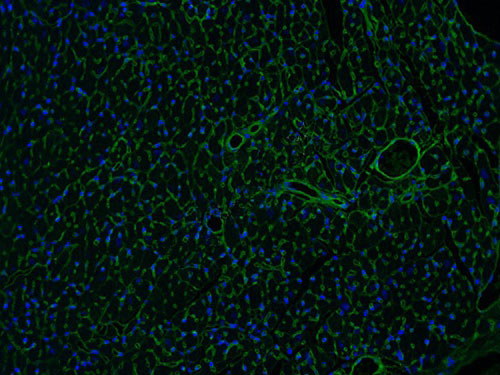

麥胚凝集素(WGA)是從谷物中提取出來,可以特異性的結(jié)合心肌細(xì)胞膜上的一種糖蛋白,二者結(jié)合起來可以將心肌細(xì)胞膜染出來。WGA可以把心肌細(xì)胞膜染出來,這樣是否肥大的細(xì)胞從圖像與正常組的對(duì)比就可以看出,也可以用專門的軟件對(duì)染出的細(xì)胞進(jìn)行直徑、面積等的測(cè)量,能夠分析心肌細(xì)胞是否肥大。

實(shí)驗(yàn)結(jié)果展示:

WGA染色-小鼠心臟

脫蠟至水-抗原修復(fù)-滴加WGA工作液,溫箱孵育30分鐘-染核封片-顯微鏡鏡檢